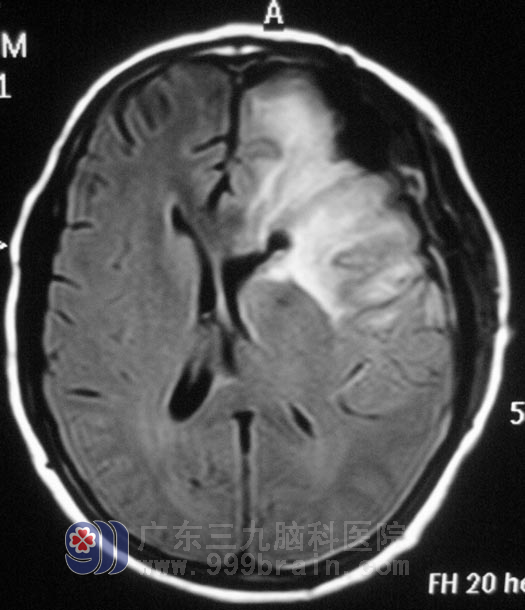

次日,卢女士在先生的陪伴下来到广东三九脑科医院,头颅MR检查,结果提示:左侧额颞叶大片异常信号影,大小约7.2cm×6.0cm×5.4cm,头颅MRS及弥散检查进一步考虑为低级别胶质瘤。鉴于卢女士的病程短、症状发展快,综合神经外科 鲁明主任指示抓紧时间完善各项术前准备。2月27日,在全麻下行左侧额叶肿瘤切除术,术中使用导航仪定位,显微镜下见左额叶局部脑组织呈灰白色色泽改变,根据术前讨论计划,术中唤醒麻醉,在患者语言配合及肢体运动情况下使用超声吸引切除肿瘤,术中对语言及肢体运动保护完好。术后卢女士未出现偏瘫、失语等手术并发症。经病理证实为:原浆性星形细胞瘤(胶质细胞瘤I-II级)。

▲手术后